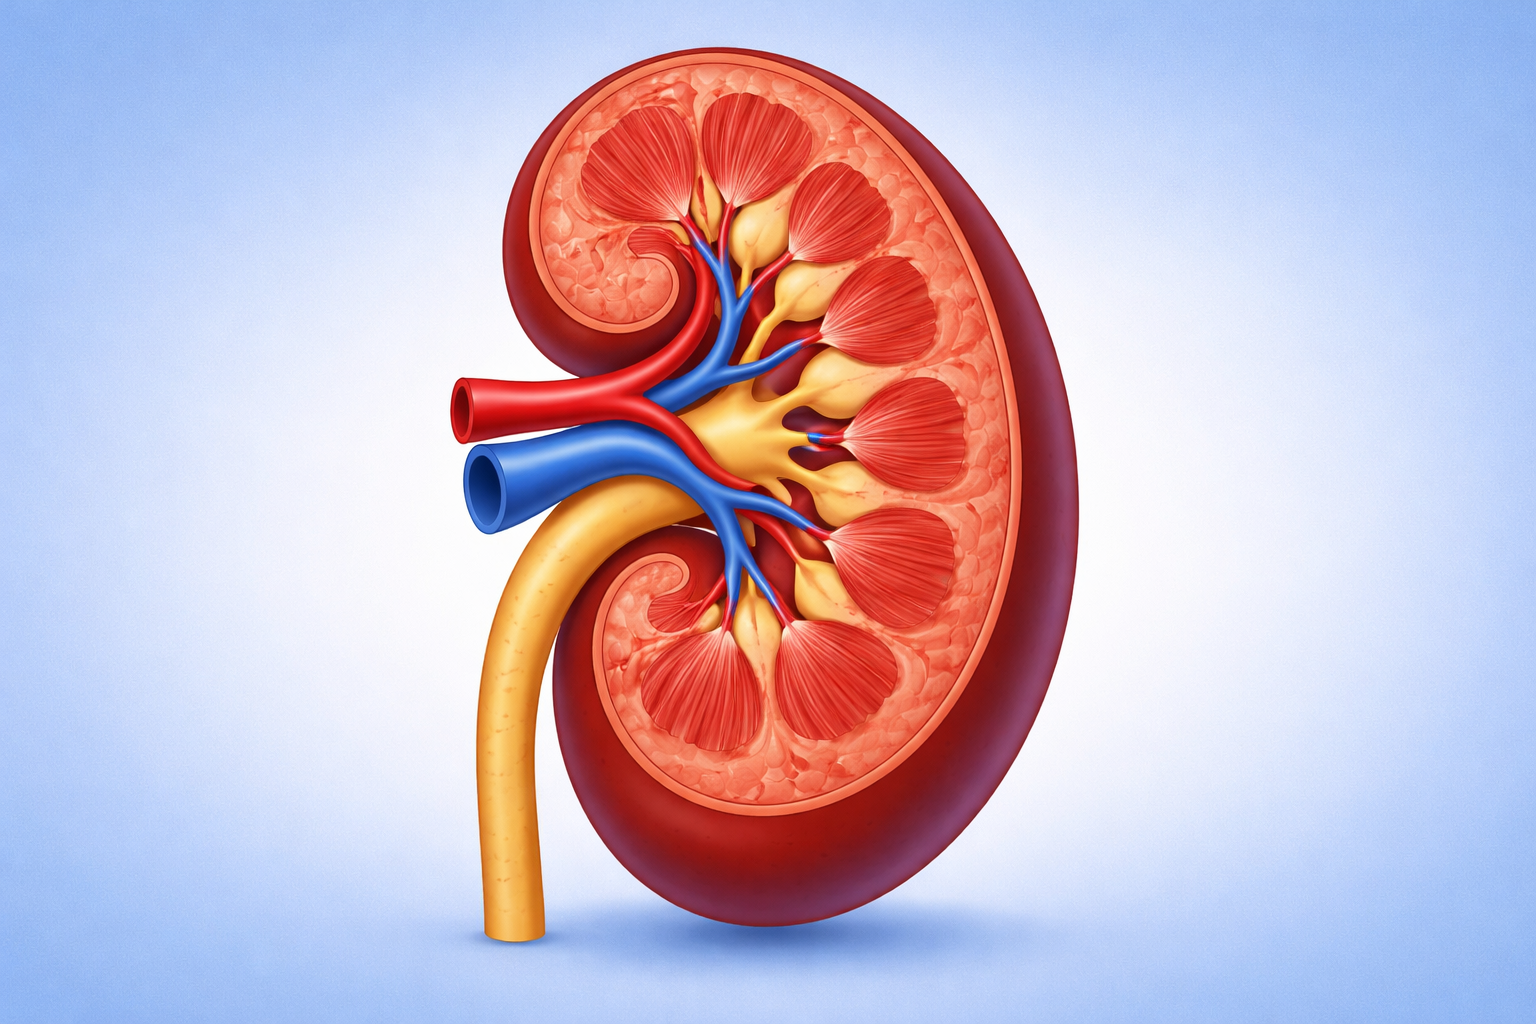

I reni svolgono funzioni essenziali per l’organismo: filtrano il sangue, eliminano le tossine, regolano l’equilibrio dei liquidi e contribuiscono al controllo della pressione arteriosa. Quando questi organi smettono di funzionare correttamente, l’intero organismo ne risente.